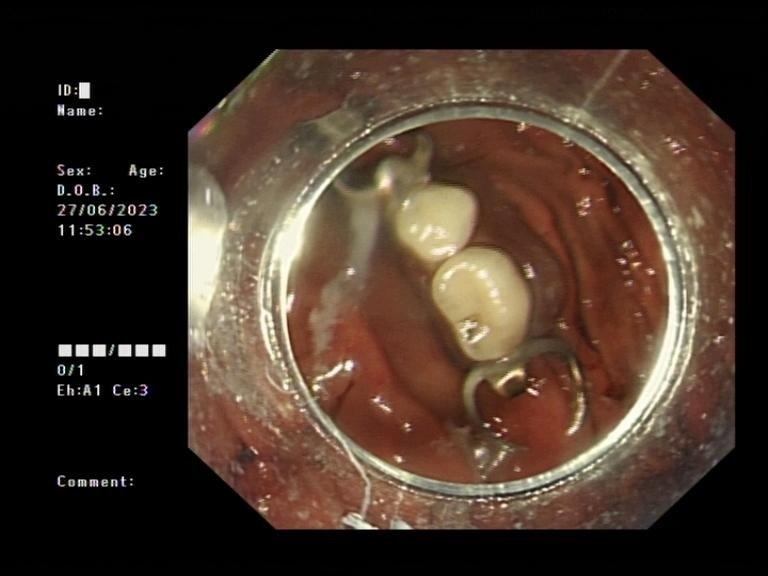

消化内科与麻醉科会诊讨论,针对朱大爷高龄的情况制定救治方案随后,消化内科蒋小猛主任为朱大爷进行胃镜手术,由于假牙有4厘米长,且二端均有二个半环形倒钩,为避免取出假牙时划破食道,蒋小猛主任用透明帽辅助,成功套取出横跨气管和食管的整排假牙。

朱大爷胃内取出的假牙